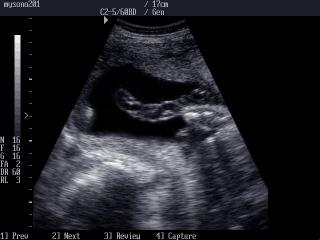

Atlas of ultrasound images - obsterics (pg. 12)

In the section "Оbsterics" of atlas the results of ultrasonic examinations of pregnant women with different durations of gestation are represented. Here you can see images of internally organs, cerebrum, cordis and the sex of the fetus, the sonograms of multiple pregnancy, the blood flow in placenta and umbilical cord, defects of fetal`s development, etc.